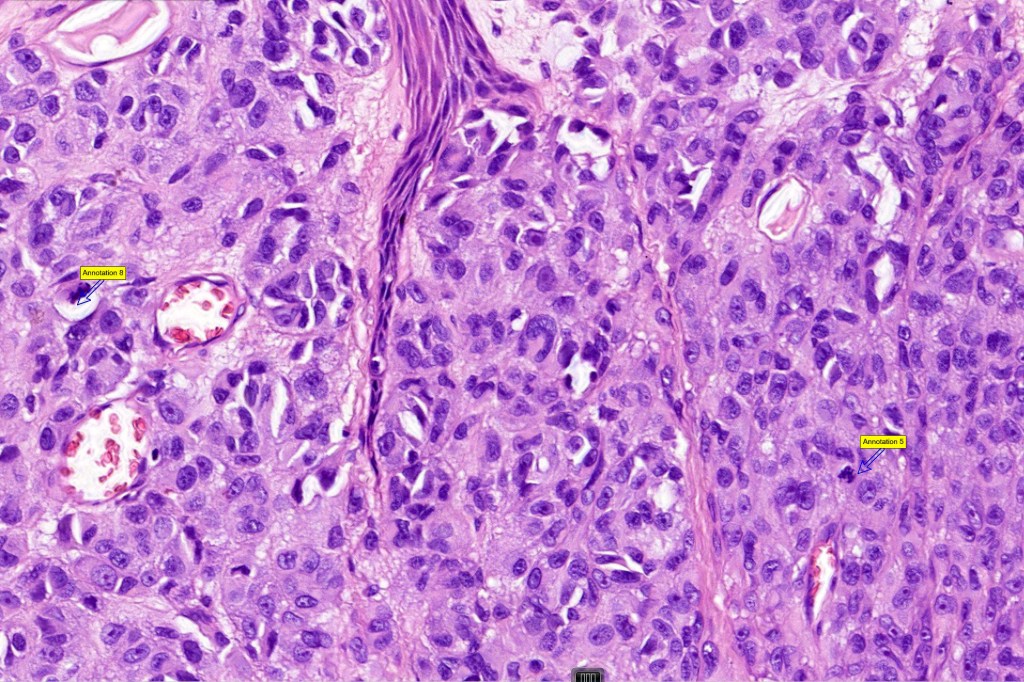

•Expansile nodules or diffuse

•Compression of connective tissue

•Subtle or not so subtle impaired maturation with depth (sometimes this is evident at scanning magnification)

•Mitoses invariable including often in the deep aspect

•S100 & SOX10 are useful to highlight impaired maturation

•HMB45 expressed throughout

•Cyclin D1 & Ki67 often show marked expression